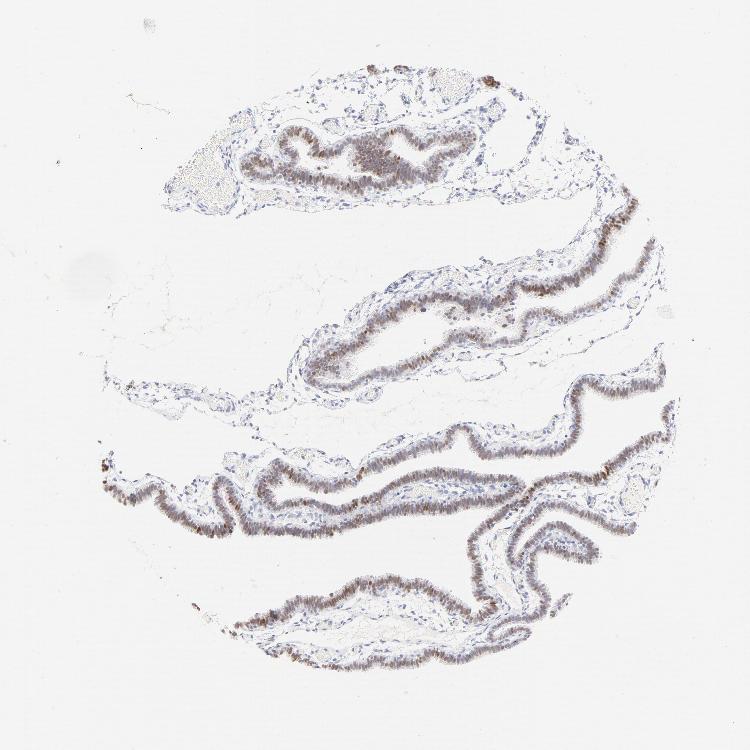

TISSUE PRIMARY DATA FALLOPIAN TUBE Show tissue menu

FALLOPIAN TUBE - Antibody stainingi

Antibody staining in the annotated cell types in the current human tissue is reported as not detected, low, medium, or high, based on conventional immunohistochemistry profiling in selected tissues. This score is based on the combination of the staining intensity and fraction of stained cells.

Each image is clickable and will lead to virtual microscopy that enables deeper exploration of all samples and also displays staining intensity scores, fraction scores and subcellular localization as well as patient and tissue information for each sample.

Antibody HPA003316Antibody HPA003479

Ciliated cells (cell body) -Low

Ciliated cells (cilia axoneme) -Not detected

Ciliated cells (ciliary rootlets) -Not detected

Ciliated cells (tip of cilia) -Not detected

Glandular cells Medium-

Non-ciliated cells -Low